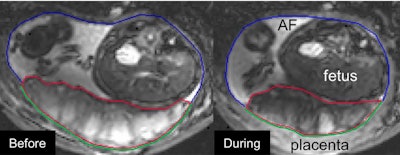

The so-called utero-placental pump reduced the area and thickness of the myometrium that underlies the placenta. It also stretched the rest of the uterine wall and reduced placental volume by up to 40%.

"The shape of the healthy placenta during contraction is similar to the thickened shape of the compromised placentas, raising the possibility that the preeclamptic placenta is permanently contracted to some extent," the authors wrote.